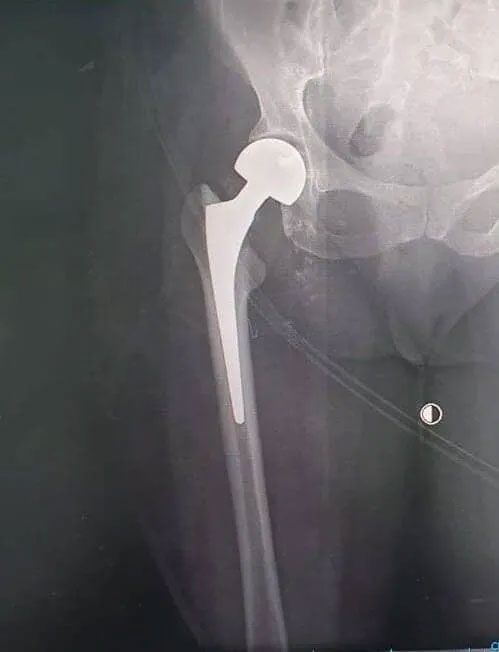

Prótesis de cadera

La prótesis total de cadera consiste en la sustitución de la articulación de la cadera que es la articulación que une el tronco con los miembros inferiores. Esta sustitución se puede realizar por gran cantidad de patologías en jóvenes, adultos y adultos mayores.

La articulación de la cadera consiste en la articulación de la pelvis con el fémur. Una de las patologías más comunes de esta articulación es la artrosis que causa dolor y disminución del movimiento, por lo que se indica la prótesis de cadera.